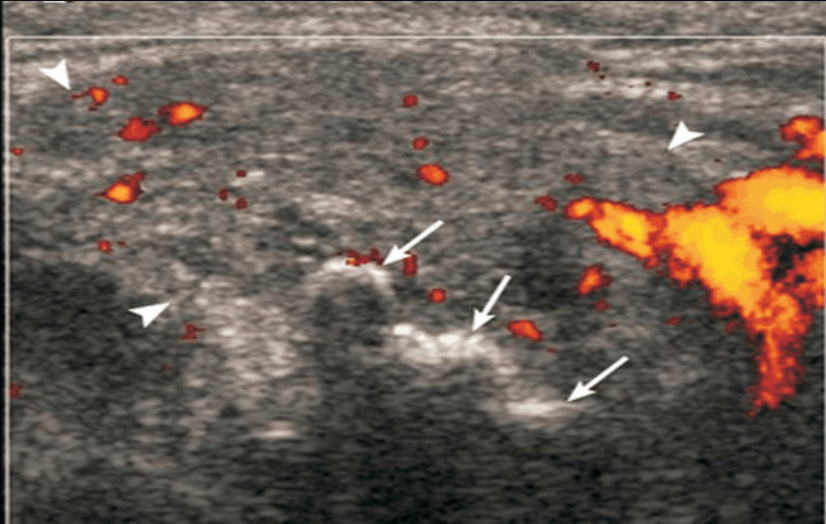

Khi siêu âm sẽ thấy tuyến nước bọt to lên và giảm âm, không đồng nhất, có vùng giảm âm nhỏ hình bầu dục và có thể có dòng máu tăng khi siêu âm màu, hạch bạch huyết to lên.

4.1 Đối với bệnh áp xe tuyến nước bọt

Hiện lên hình ảnh khi siêu âm là các tổn thương giảm âm hoặc trống âm có tăng âm phía sau, bờ không rõ, các chấm âm có thể nhìn thấy bên trong ổ áp xe do các bọt khí nhỏ. Các ổ áp xe được tổ chức hóa có thể có một quầng tăng âm bao quanh.

4.2 Đối với viêm tuyến nước bọt mãn tính

Bệnh nhân bị viêm tuyến nước bọt mạn tính khi siêu âm sẽ thấy nhiều bùng nhỏ hình tròn hoặc hình bầu dục giảm âm, các tổn thương phân bố khắp nhu mô tuyến...